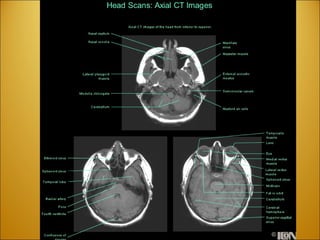

Divisions of the Brain FOREBRAIN (PROSENCEPHALON) TELENCEPHALON DIENCEPHALON MIDBRAIN (MESENCEPHALON) MESENCEPHALON HINDBRAIN (RHOMBENCEPHALON) ) METENCEPHALON MYELENCEPHALON

FOREBRAIN (PROSENCEPHALON) TELENCEPHALON DIENCEPHALON